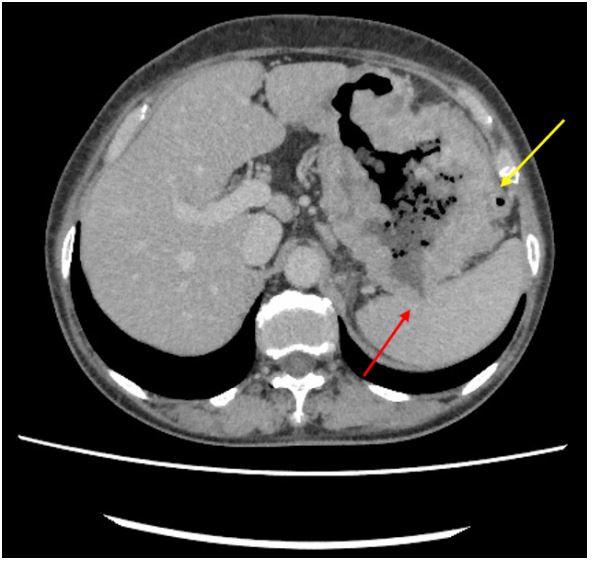

An eighty-year-old woman presented with the symptoms of abdominal pain, slight fever of 37-38°C, and body weight loss. Upper Gastrointestinal (GI) examination performed one month prior to presentation revealed a gastric tumor, while Esophagogastroduodenoscopy (EGD) showed a type 3 tumor in the gastric fundus and corpus (Figure 1a). However, food residues covering the tumor surface prevented precise observation. Colonoscopy revealed an irregular surface elevation in the splenic flexure of the colon (Figure 1b), in which an adenocarcinoma was detected by biopsy. Contrast-enhanced computed tomography (eCT) revealed advanced GC with extensive invasion of the transverse colon, spleen, and pancreas (Figure 2a,b). Peritoneal dissemination and lymph node metastasis were suspected. The eCT image also showed gas in the pancreatic duct, indicating fistulation from the stomach to the pancreatic duct due to tumor invasion (Figure 2b). This fistula was presumed to be the cause of the patient’s low-grade fever. Thus, relatively rapid surgery was performed to control bacterial infection of the pancreatic duct and ensure resection of the advanced GC. Open surgery was performed, and extensive invasion of the GC into the pancreas and transverse to the descending colon was detected. Fortunately, no obvious peritoneal dissemination was observed. Therefore, a total gastrectomy with D2 lymphadenectomy combined with distal pancreatectomy, partial colectomy, and cholecystectomy was performed. Cholecystectomy was added as it is performed along with total gastrectomy as the standard procedure in our institute. The resected gastric tumor measured 160×80 mm (Figure 3a). Pathological tests revealed a poorly differentiated adenocarcinoma of the stomach invading the pancreas, transverse colon, and splenic serosa (Figure 3b-e). No metastasis was identified in the dissected lymph nodes or peritoneum. The pathological cancer stage was IIIA, according to both the TNM Classification of Malignant Tumours-8th edition [13] and the 15th edition of the Japanese Classification of Gastric Carcinoma[14]. Approximately two months after surgery, we initiated adjuvant chemotherapy with tegafur/gimeracil/oteracil, which was discontinued after only two months due to severe adverse events. Two years after surgery, the patient remains alive without relapse.

Figure 2a: Invasion of gastric cancer to the splenic serosa (red arrow) and transverse colon (yellow arrow) was suspected based on eCT results.

Figure 2b: Gastric cancer invasion to the pancreatic body and tail (red arrow). Air can be seen in the pancreatic duct (yellow arrow).